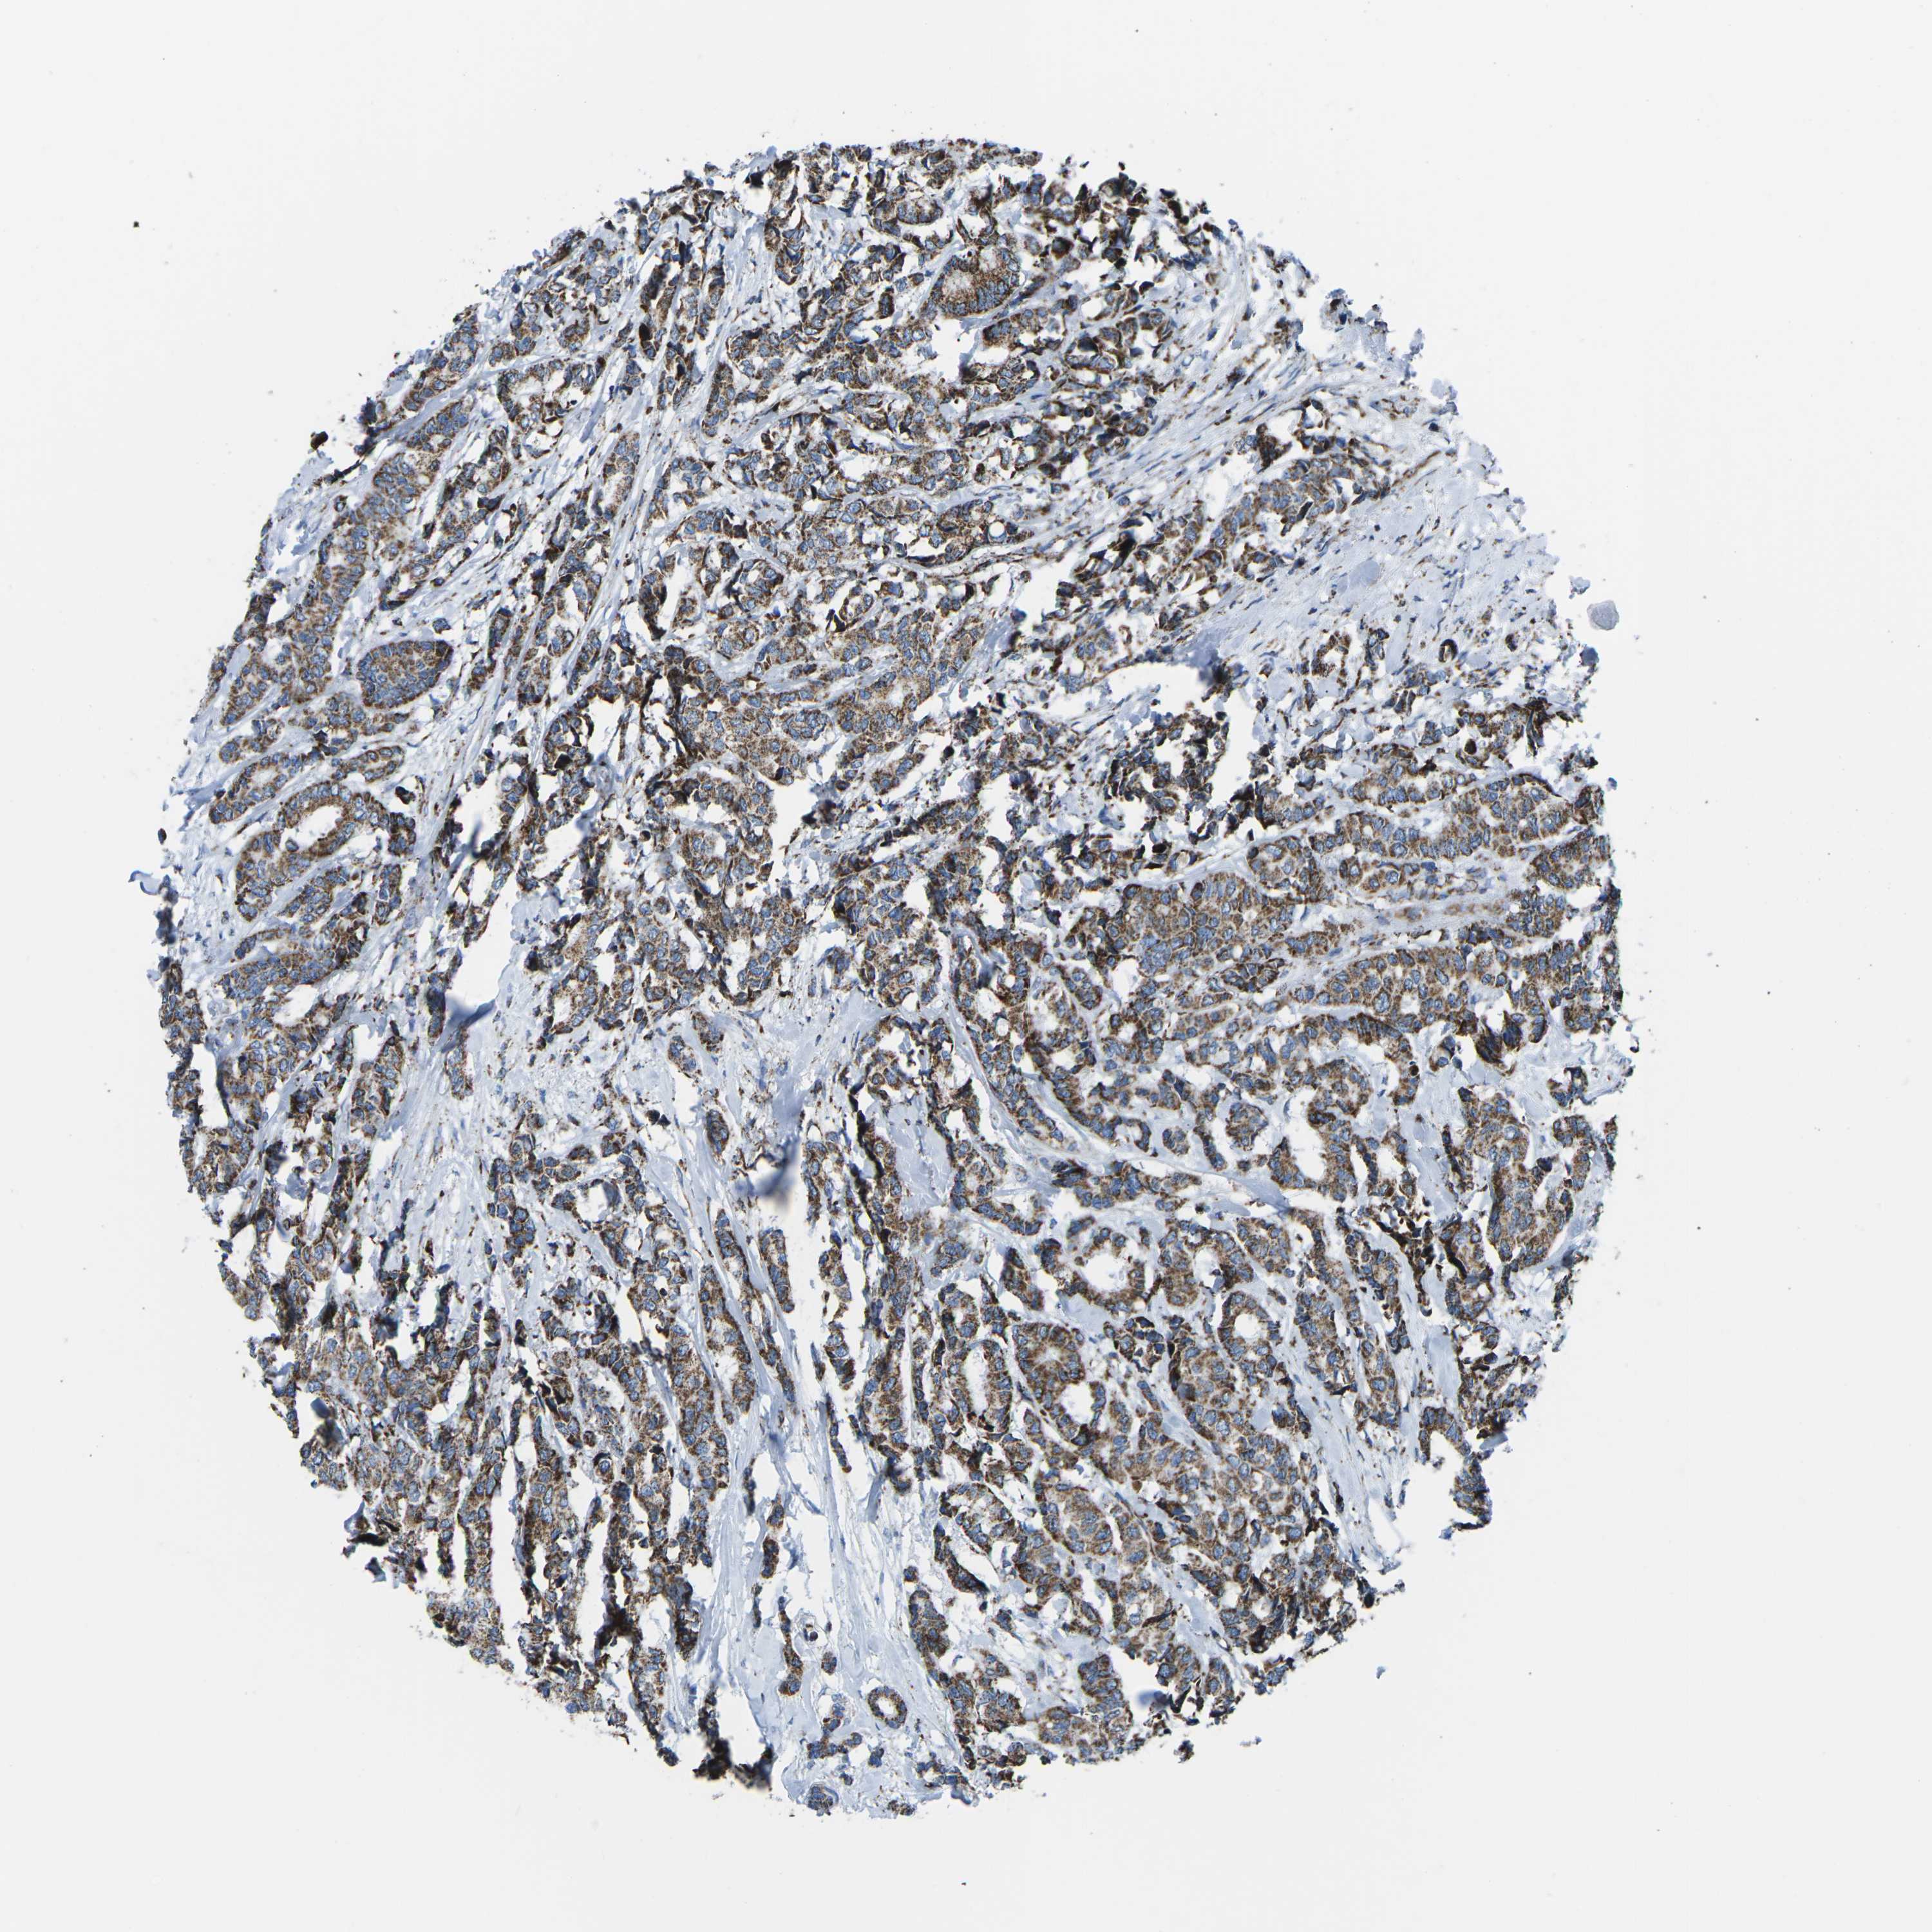

CANCER BREAST CANCER Show tissue menu

BRCA TCGA BRCA VALIDATION PROTEIN EXPRESSION

ANTIBODIES

AND

VALIDATION